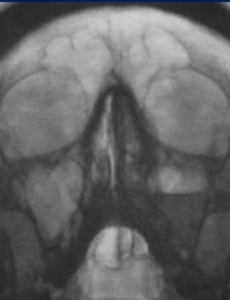

Также были выявлены деструктивные изменения верхней челюсти с утолщением и эмфиземой мягких тканей лицевой области слева (рис. 7). Пациент был переведен в специализированное отделение. Проведена секвестрэктомия верхней челюсти, удаление зубов слева. В гистологических препаратах послеоперационного материала выявлены нити мицелия. При пересмотре гистологического материала в НИИ Медицинской микологии им. П. Н. Кашкина, был обнаружен широкий несептированный мицелий, характерный для мукоромицетов. На основании клинической картины, данных КТ и микологического обследования был диагностирован COVID-ассоциированный мукормикоз околоносовых пазух и структур орбиты. Назначили антимикотическую терапию: введение липосомального амфотерицина В 10 мг/кг в сутки, после стабилизации состояния переход на пероральную терапию. По месту ведения пациента была начата антимикотическая терапия липидным амфотерицином В 14 дней, далее амфотерицином В дезоксихолатом, который был отменен ввиду нефротоксичности. В последующем лечение продолжили изавуконазолом в стандартной дозе. Согласно международным рекомендациям, проводился контроль уровня глюкозы крови и произведена отмена ГКС. Общая продолжительность лечения составила 105 дней. Ежедневно в первую неделю, затем по мере необходимости проводили осмотр области оперативного вмешательства с местной обработкой слизистых оболочек препаратами амфотерицина В. После проведенной антимикотической терапии на контрольных МСКТ ОНП выявили признаки стабилизации мукормикоза в виде отсутствия прогрессирования процесса; склерозирования, утолщения и гиперостоза костей; уменьшения отека и утолщения мягких тканей с их фиброзированием (рис. 8, 9).